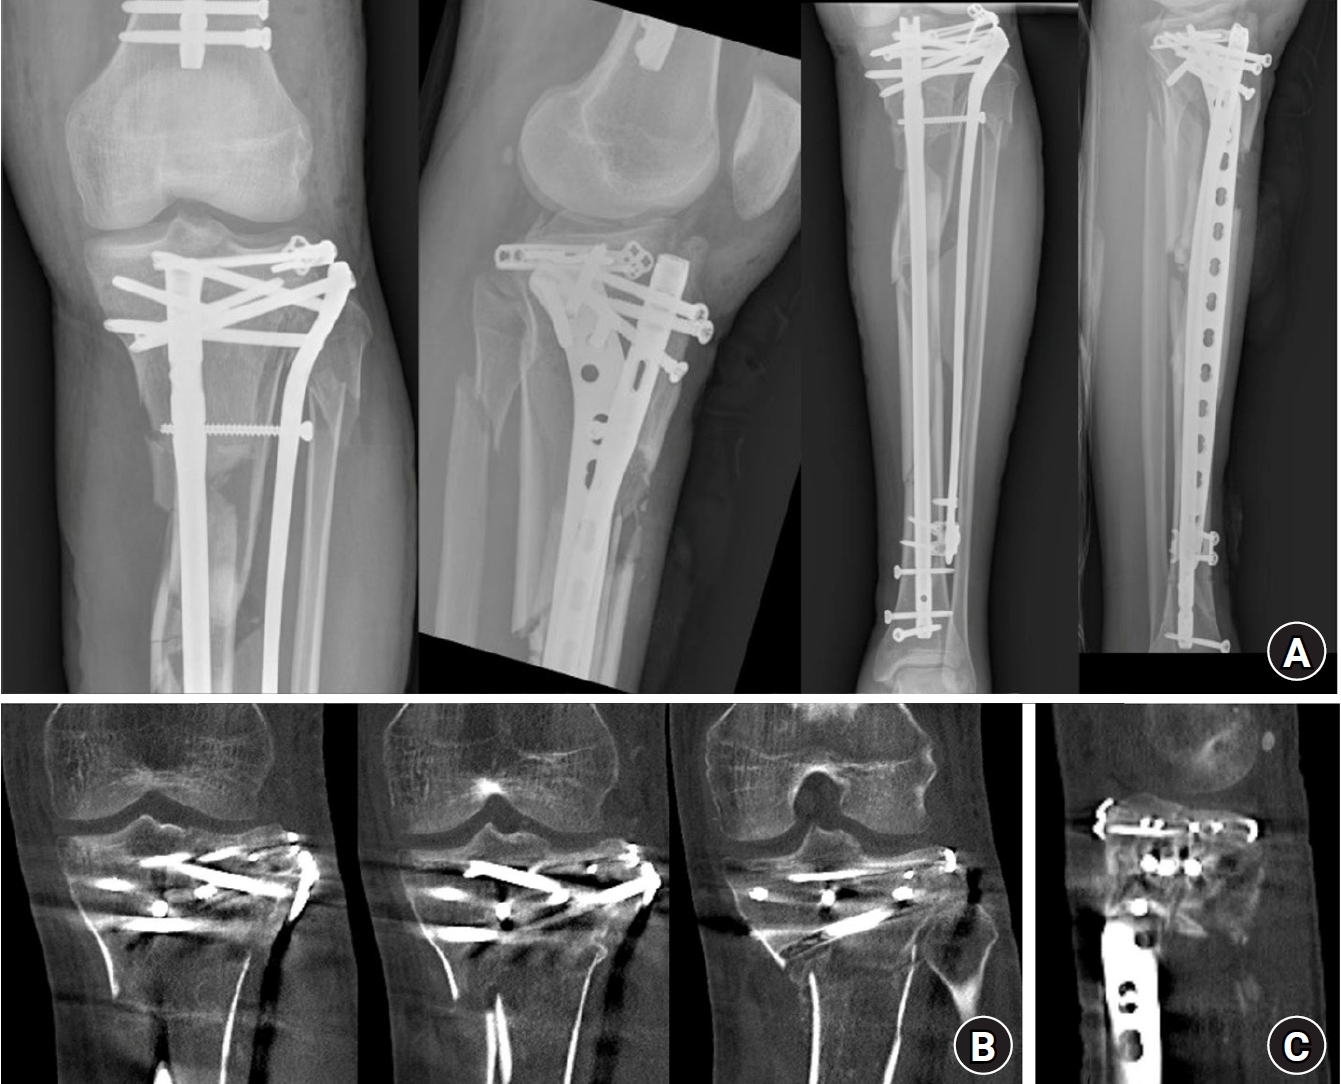

Fig. 3.

Postoperative plain radiographs and computed tomography (CT) images. (A) Postoperative plain radiograph. (B) Axial CT image confirming that screws from the rim plate did not interfere with the intramedullary nail trajectory. (C) Coronal CT image after fixation. (D) Sagittal CT image after fixation.

Fig. 3. Postoperative plain radiographs and computed tomography (CT) images. (A) Postoperative plain radiograph. (B) Axial CT image confirming that screws from the rim plate did not interfere with the intramedullary nail trajectory. (C) Coronal CT image after fixation. (D) Sagittal CT image after fixation.

The procedure started by placing a rim plate to convert the tibial plateau fracture into a single articular segment. The surgical approach was chosen based on the fracture pattern. The patient had posterolateral and anteromedial tibial plateau fractures. To address the posterolateral fracture, a modified anterolateral approach was employed, extending through the space between the fibular collateral ligament (FCL) and the posterolateral plateau rim [7,8]. The anteromedial fracture was approached through an anteromedial incision of approximately 5 cm, extending from the proximal medial open wound. Long incisions were not required, as the exposure was sufficient for fracture reduction and rim plate placement. The medial collateral ligament was incised longitudinally at the fracture site to confirm intraarticular reduction. The posterolateral plateau fracture was reduced using a colinear clamp. A 2.7-mm variable-angle locking compression plate (VA-LCP; Variable Angle LCP Forefoot/Midfoot System 2.4/2.7, Synthes GmbH) was contoured and inserted into the posterolateral space beneath the FCL. The contoured plate and posterolateral fragment were pressed together with a pointed reduction bone clamp (Fig. 2A and 2B). To maintain compression, a 2.7-mm cortical screw was inserted into the most anterior hole, followed by 2.7-mm locking screws to secure the plate and connect the posterolateral fragment with the anterolateral main fragment at the plateau rim. On the anteromedial side, another 2.7-mm VA-LCP was contoured and positioned over the medial collateral ligament. A pointed bone reduction clamp was used to achieve medial-to-lateral compression, and 2.7-mm locking screws were inserted. This construct restored the tibial plateau as a single segment (Fig. 2C and 2D). In these procedures, care was taken to avoid directing screws toward the anterior center, which could obstruct IM nail passage. However, most screws—being oriented nearly perpendicular to the cortical surface and positioned within the allowable variable screw angulation of up to 30°—generally do not interfere with the trajectory of the IM nail. Therefore, it was sufficient to ensure that screws inserted through the anterior holes of the plate did not point excessively anteriorly. Once the plateau was stabilized as a single segment, IM nailing was performed through the suprapatellar approach to minimize the displacement of the proximal fragment. To prevent the displacement of the plateau segment during nail entry, both the tibial tuberosity and posterolateral aspect were secured with a pointed bone reduction clamp (Fig. 2E). During nailing, overall lower limb alignment was confirmed using the alignment rod before screw fixation. Only three cancellous screws could be inserted into the proximal segment. Additional anterolateral tibial plating was performed to improve the stability of the construct. A 4.5-mm LCP Proximal Tibia Plate (Synthes GmbH) was positioned using a MIPO technique. Fine adjustment of the plate position enabled linkage with the IM nail, a process that was technically straightforward. A drill sleeve was inserted through the proximal aiming arm of the IM nail (Expert Tibia Nail, Synthes GmbH), and the plate was adjusted to precisely align with the drill sleeve. Subsequently, 5.0-mm interlocking screws were inserted through the plate holes, connecting the transverse locking hole and the oblong slot of the IM nail to link the nail and plate (Fig. 2F and 2G). More 5.0-mm locking screws were added to the proximal holes of the plate to secure it to the proximal tibial section. For distal fixation, one 4.5-mm cortical screw and several 3.5-mm locking screws were inserted using a 3.5-mm locking attachment plate (Synthes GmbH). This was performed to avoid interference with the IM nail, completing the final fixation. Finally, the open wounds on the anteromedial aspect of the tibia were closed directly because no medial plate was applied. Postoperative plain radiographs and computed tomography (CT) images are shown in Fig. 3.